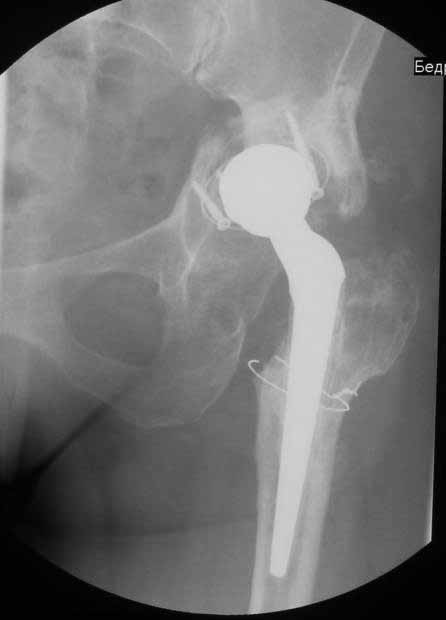

Уважаемые коллеги. Хотелось бы услышать мнения и советы по представляемому случаю. Пациентка 45 лет. Бесцементное эндопротезирование левого тазобедренного сустава 6 лет назад (впадина RM, Mathys, металл-металл, ножка Зульцеровская). За 10 лет до протезирования – коррегирующая остеотомия бедренной кости, которая не срослась в течение года до удаления пластины, а затем срослась в течение 3 месяцев иммобилизации в кокситной повязке. После протезирования получилось наблюдать пациентку почти постоянно, поскольку через 2 года синтезировал ей лодыжки на оперированной стороне, затем, через несколько месяцев удалил фиксаторы, а в 2009г. резецировал мениск на противоположной стороне. Боли все эти годы не беспокоили. Пациентка чуть выше среднего роста, вес тела нормальный. Физические нагрузки переносила хорошо. Работает на 7 этаже без лифта. Год назад экстирпация матки по поводу лейомиомы больших размеров. Несколько месяцев назад появились боли в области левого тазобедренного сустава. При рентгеновском и КТ исследованиях (июль с.г.) – нестабильность тазового компонента. От предложенной замены протеза пациентка на тот момент, слава богу, отказалась. Через какое то время боли в области левого тазобедренного сустава практически полностью прошли, а около 2 месяцев назад появилось ощущение патологической подвижности таза и боли в паху справа, которые через некоторое время уменьшились, а потом снова усилились после значительных физических нагрузок (много ходила по песку на пляже, носила тяжести). Ежедневно принимала диклофенак. На рентгенограммах – переломы правой лонной кости. Сейчас госпитализирована из-за болей в паху справа. Боли слева не беспокоят. На фоне снижения нагрузок в стационаре боли значимо уменьшились. Способна ходить без средств дополнительной опоры.В анализах крови чуть повышены трансаминазы и гамма-ГТ, моча без особенностей.

Вопросы: -правильно ли я расцениваю переломы как стрессовые на фоне неполноценного таза (pelvic insufficiency stress fractures)? -Можно ли так же расценить ситуацию на стороне протеза и, соответственно, не торопиться с ревизией, рассчитывая на вторичную стабилизацию? Уж больно не хочется менять ножку. -Если думать о ревизии, то когда? На представленных снимках тазобедренный сустав до и сразу после операции, затем 2 снимка 2009г., когда ничего не беспокоило, затем КТ 2-х месячной давности и вчерашние рентгенограммы обоих тазобедренных суставов.

При сравнении рентгенограмм можно увидеть насколько чашка переместилась от места своего первичного расположения. От опрокидывания ее удерживают конструкционные элементы "рожки". Без них ситуация, возможно, уже была бы катастрофической (чашка в тазу). Думаю надежды на вторичную интеграцию, могут быть обмануты и ревизии не избежать.

Вопрос о замене ножки зависит от ее стабильности и длины конечности. Если уже сейчас нога длиннее или после вмешательства центр ротации низведется - придется ногу менять.